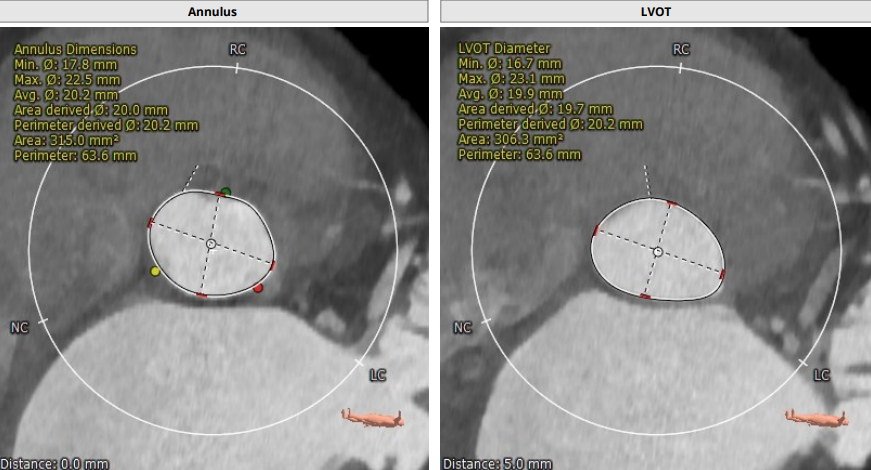

CT评估报告

瓣环平均直径:20.2 mm,左室流出道平均直径:19.9mm

升主动脉(未见)明显扩张,心脏角度:55°

左冠高度:12.5 mm,右冠高度:13.6 mm

Annulus:20.2mm;LVOT:19.9mm

Sinus:25.3mm*25.2mm*24.7mm ;STJ:23mm*24mm

升主:27.6mm*29mm;主动脉成角:55°